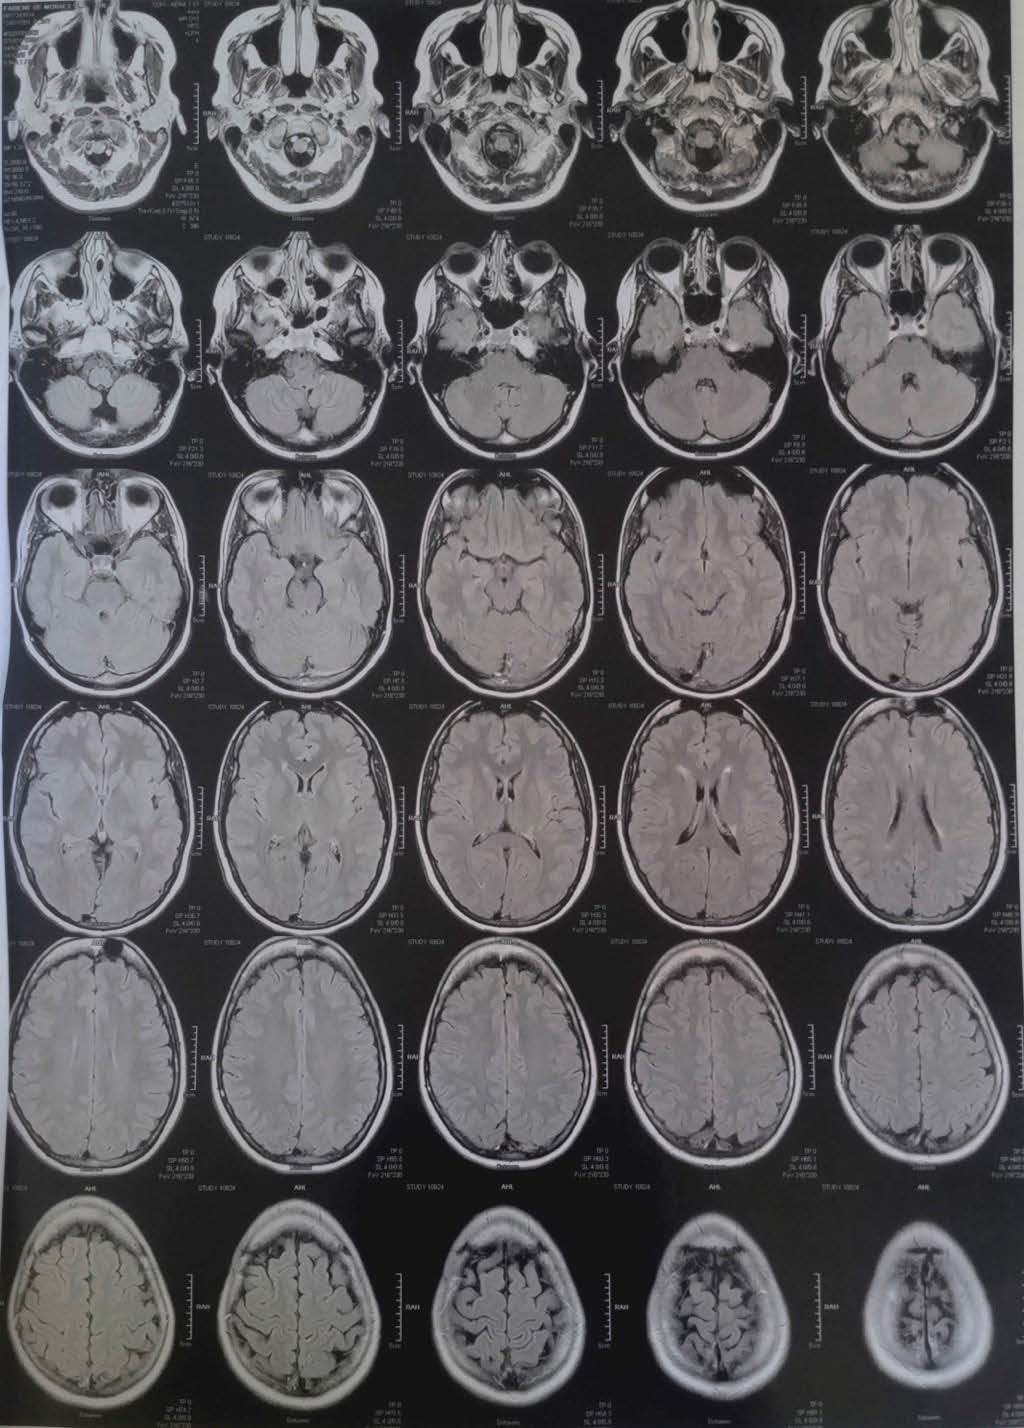

Seus sintomas são extremamente variáveis e dependem da localização e da gravidade de cada ataque inflamatório, chamado de surto. Podem ser: dormência, dor, formigamento, perda de equilíbrio e coordenação, dificuldade para caminhar, transtornos visuais, incontinência intestinal e urinária, diminuição da capacidade de atenção, perda de memória, transtornos fonoaudiólogos, cognitivos e emocionais, fadiga, entre outros. Ou seja, uma gama imensa de alterações motoras, sensitivas, visuais e cognitivas, que podem ser temporárias ou permanentes. O diagnóstico da doença é feito através de um exame clínico combinado com outros laboratoriais, que na maior parte das vezes serve para descartar outras doenças. Desses exames, o mais importante é a ressonância magnética, um exame que cria imagens de alta definição de órgãos internos através de um campo magnético.

Primeira ressonância magnética e a descoberta do interior do crânio.

Sem ter conhecimento do procedimento a ser adotado, fui ao exame sozinha. Nele, fiquei cerca de uma hora dentro de uma máquina com um acesso no braço para inserção de contraste, um protetor auricular para amenizar o forte barulho do exame, e um capacete para me manter imóvel durante o período necessário. Ninguém me explicou que eu deveria respirar docemente para não interferir na imagem produzida, e não precisar refazê-la. Dentro da máquina, o som era ensurdecedor. Tão alto que vibrava em meu corpo. Variava entre o grave e agudo, rápido e repetitivamente. Chegava a durar minutos sem intervalo. A abertura da máquina para entrada do meu corpo era pequena e eu me sentia sufocada. Descobri-me claustrofóbica.

Os pontos brilhantes das inflamações ativas.

Ao voltar à neurologista com o resultado da ressonância magnética, descobri que eu tinha inflamações ativas no cérebro, no cerebelo e na coluna cervical. Havia forte indicação de que eu tinha esclerose múltipla, mas ainda era preciso descartar seis outras possibilidades. A médica recomendou uma internação hospitalar no dia seguinte para realização de uma pulsoterapia com altas doses de um corticoide, a fim de conter o processo inflamatório. Em um primeiro momento, não entendi a gravidade do problema, os sintomas já tinham passado e eu me sentia bem. A médica precisou ser incisiva: as inflamações poderiam gerar sequelas irreversíveis.

Os exames não ficam mais fáceis ao longo dos anos. Mas pacientes desenvolvem estratégias para lidar com eles. Se nas primeiras experiências eu era surpreendida a cada novo procedimento, nos anos seguintes eu escolhia até aonde iria com as investigações. Para as ressonâncias magnéticas, que após o diagnóstico chegaram a durar mais de duas horas, por exemplo, passei a ir acompanhada e tomar um ansiolítico para suportar, imóvel, o tempo dentro da máquina. A indicação de novos remédios para conter os efeitos de outros, ou de exames, era uma prática recorrente nas consultas médicas realizadas.